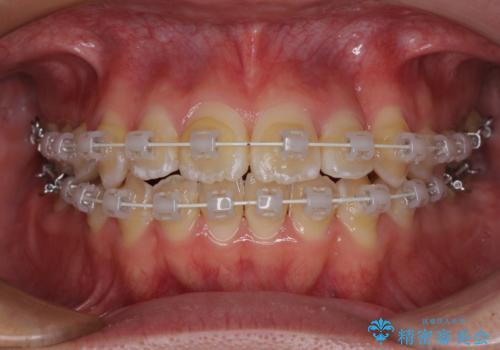

当初予定通り、1年間で治療を終えることができました。